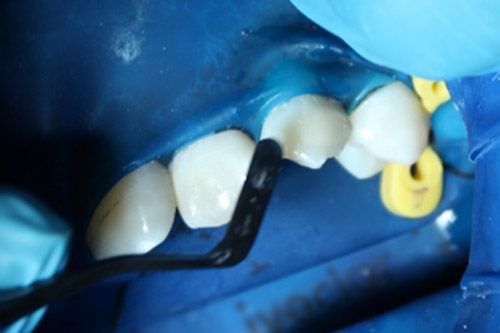

En la cavidad se colocó una resina compuesta, se le pulió con discos de lija superfix y se le dio brillo con un disco de fieltro impregnado con pasta Polimax de TDV.

Resultado final